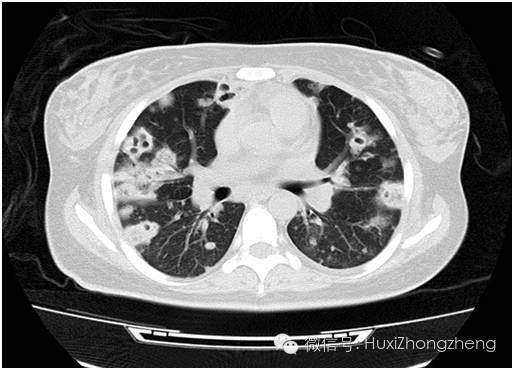

15:00 患者转入MICU,经对症处理后,患者病情稳定了。19:20患者的CT出来了,我透过群里几百条信息,可以看出各级医生已经对这个北京女孩的诊断讨论了一潮又一潮。肺部感染:真菌?奴卡?结核?治疗方案也讨论了一波又一波。检查报告分析了一次又一次。患者的腹部CT引起了詹庆元教授的格外重视:患者右侧缩小,左肾扩大。虽然值班医生已经反复确认患者没有尿频、尿急、尿痛及腰痛、血尿等症状,小便及肾功能也未见任何异常,但是眼尖的詹主任哪能放过蛛丝马迹。在这里,对于病因的追查永远没止境,这是这个团队的早已养成的素养。

图1 这么多洞洞,是什么东东?